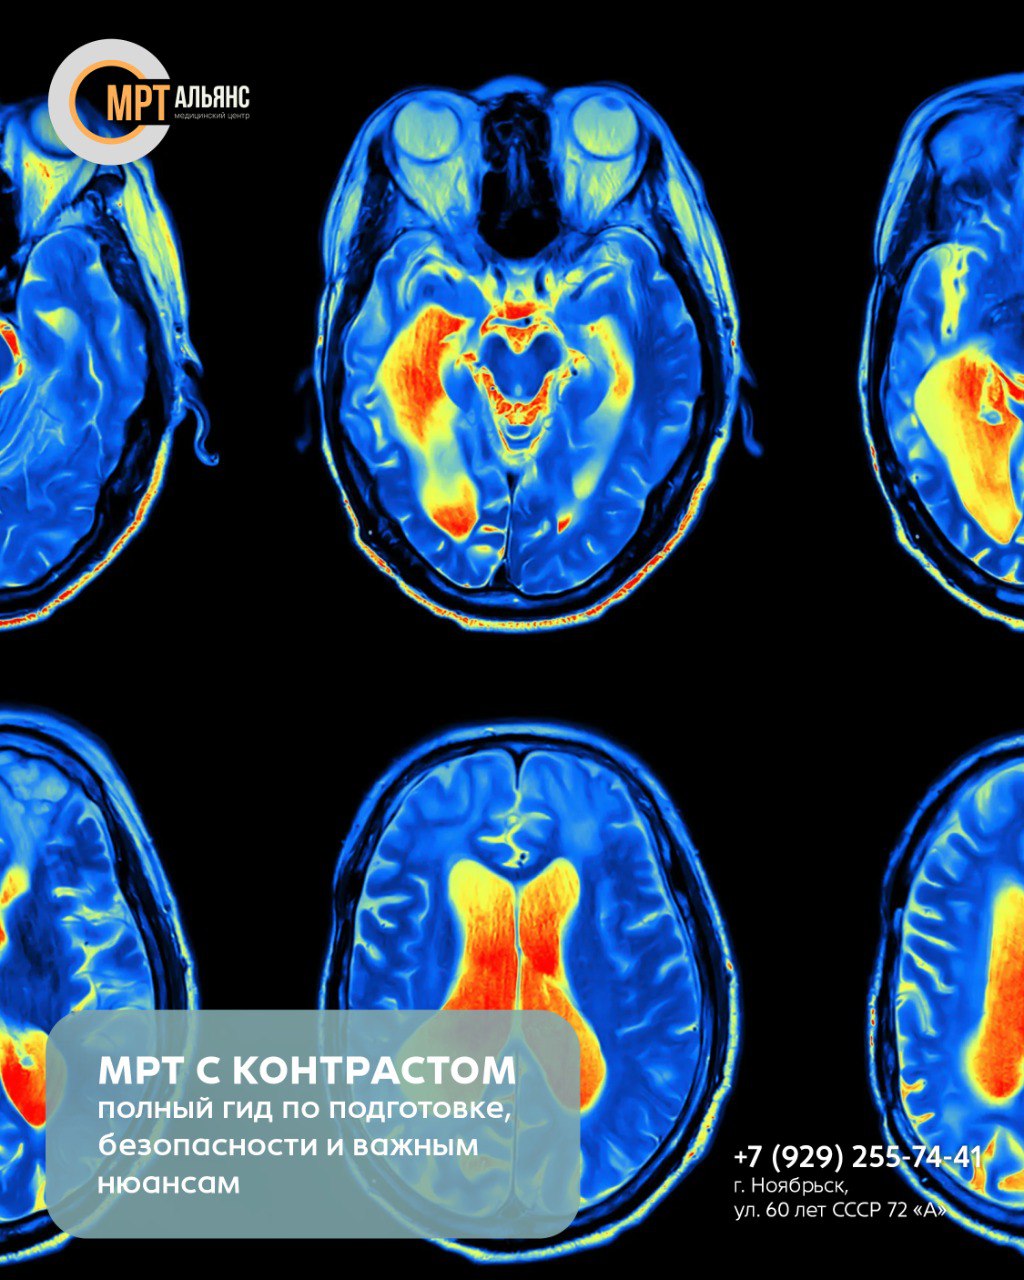

Контраст на основе гадолиния вводится внутривенно и «подсвечивает» сосуды, ткани и патологические очаги, делая изображения в 2-3 раза четче. Это позволяет выявить опухоли размером до 1 мм, воспаления и сосудистые аномалии. Вещество быстро выводится почками, но требует осторожности при аллергиях и хронических заболеваниях